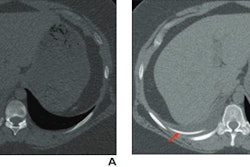

The New England Journal of Medicine’s “Image Challenge” is an online quiz that provides real clinical images and a short text description that includes details about a patient’s symptoms and presentation. It asks users to choose the correct diagnosis from multiple-choice answers. The quiz includes CT, x-ray, pathology, MRI, and macroscopic clinical images.

In one example, the AI model was provided with a photo of a patient’s arm with two lesions, which physicians would easily recognize as being caused by the same condition. Yet the lesions were presented at different angles, which caused the illusion of different colors and shapes, and GPT-4V failed to recognize that they could be related to the same diagnosis, NIH said.